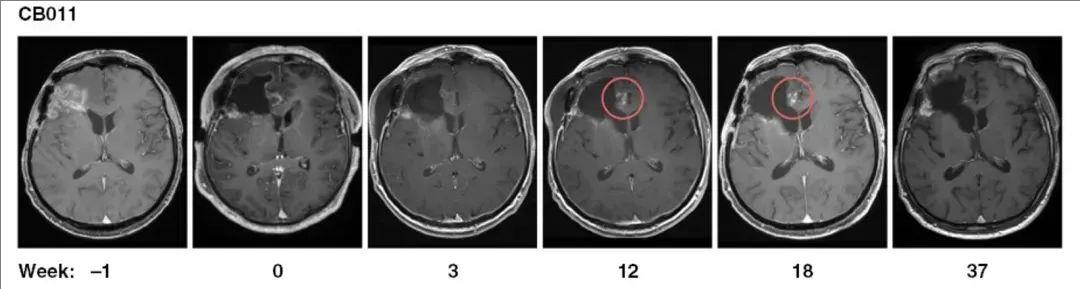

1、病情稳定及假性进展:影像学检查显示,56%(5例)的患者在复发手术和持续7~37周的CAR-NK治疗后,达到病情稳定(SD)。另2例患者在注射部位出现了假性进展,提示存在治疗所诱导的免疫反应。其中,1例患者在CAR-NK注射后第12周,复查MRI显示,切除边缘切除边缘周围,出现斑点状对比增强,并在接下来的几周内消失,可能与诱导的免疫反应相关,无需进一步治疗(详见下图)。

▲图源“Neuro-Oncology”,版权归原作者所有,如无意中侵犯了知识产权,请联系我们删除